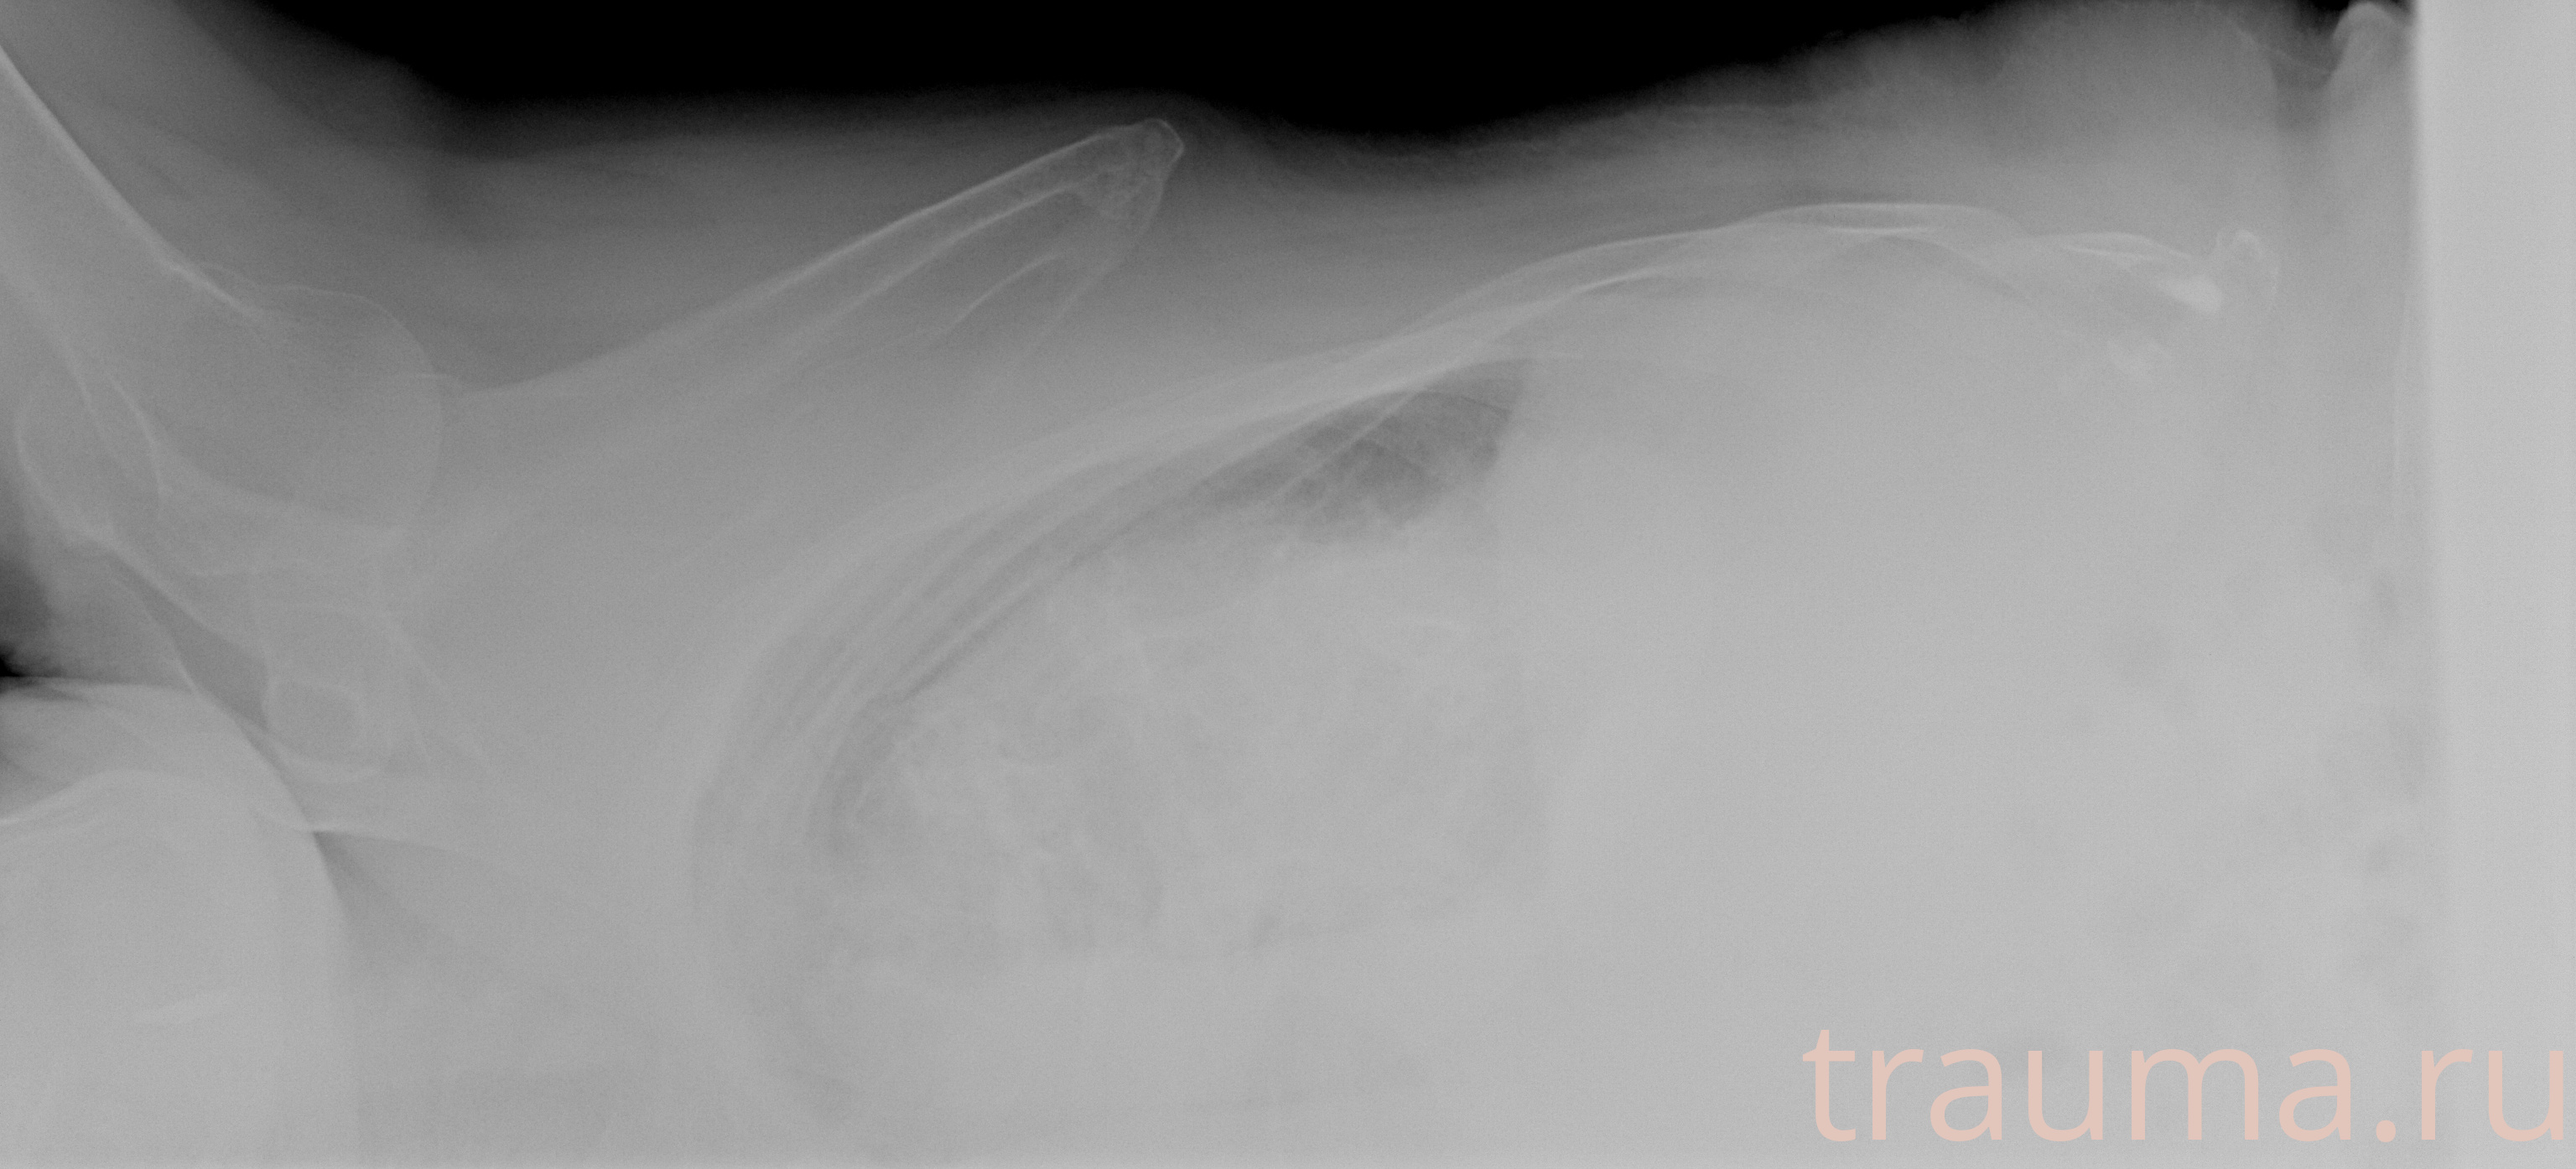

Рентген на дому: по вашему адресу приезжает врач-рентгенолог, травматолог-ортопед с мобильным рентгеновским аппаратом, проводит диагностику травмы или заболевания, делает необходимые рентгенограммы, дает рекомендации по дальнейшему лечению. Получить качественные снимки в домашних условиях возможно благодаря уникальной методике, разработанной МосРентген Центром для института  Склифосовского

при переломе шейки бедра и пневмонии от компании МосРентген Центр - партнера Института имени Склифосовского